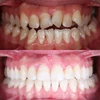

Zirkonyum uygulamalar

Porselen uygulamaları

Laminate veneer